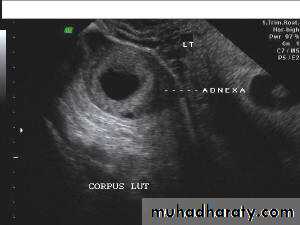

Lt. adnexal cystic mass- Luteal cyst(Lt. ovary):

Ultrasonography in Gynaecology

• Functional cysts of the ovary – Corpus Luteum cysts